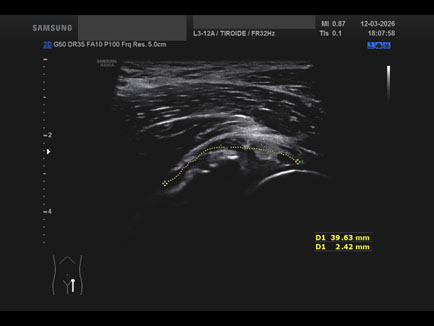

Data inserimento: 23/03/2026

Ecografia del: 12/03/2026

Strumento: Samsung

Sonda: Lineare

Commento all'esame: ganglio del cercine cotiloideo.

Conclusioni: ganglio del cercine cotiloideo (ganglion of the cotyloid labrum).

Realizzazione: Dr. F. Pietro Tarini - Gubbio (PG)

Presentazione: Dr. Massimo Dolciotti - Ancona